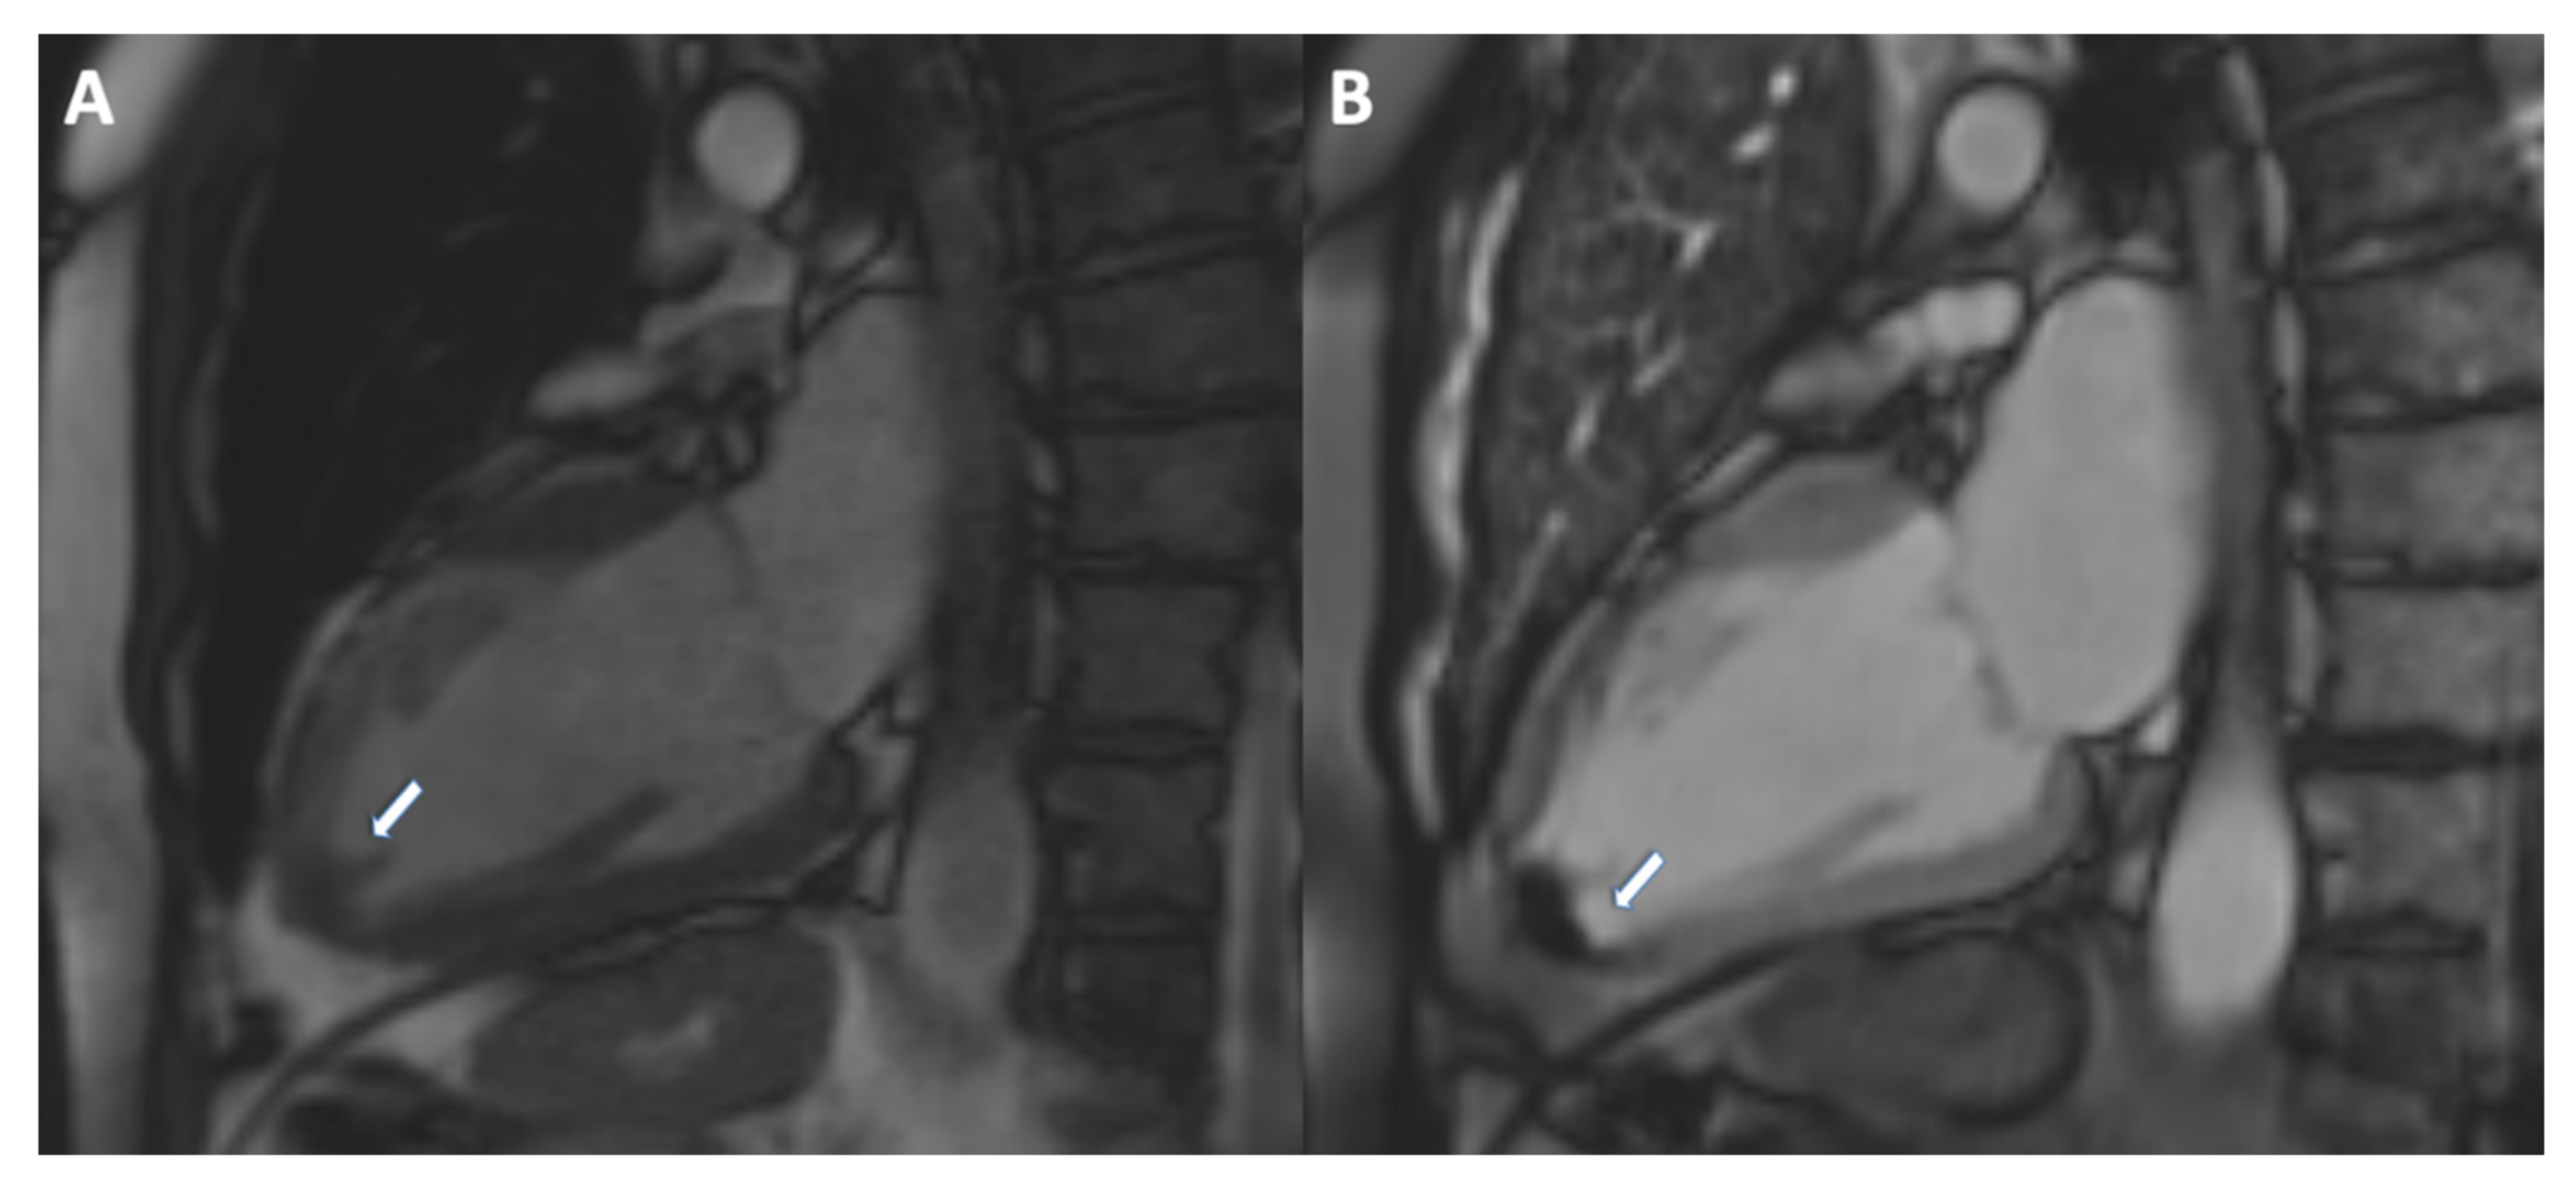

- Delewi, R.; Zijlstra, F.; Piek, J.J. Left ventricular thrombus formation after acute myocardial infarction. Heart 2012, 98, 1743–1749. [Google Scholar] [CrossRef]

- Motwani, M.; Kidambi, A.; Herzog, B.A.; Uddin, A.; Greenwood, J.P.; Plein, S. MR Imaging of Cardiac Tumors and Masses: A Review of Methods and Clinical Applications. Radiology 2013, 268, 26–43. [Google Scholar] [CrossRef]

- Roifman, I.; Connelly, K.A.; Wright, G.A.; Wijeysundera, H.C. Echocardiography vs Cardiac Magnetic Resonance Imaging for the Diagnosis of Left Ventricular Thrombus: A Systematic Review. Can. J. Cardiol. 2015, 31, 785–791. [Google Scholar] [CrossRef]

- Caspar, T.; El Ghannudi, S.; Ohana, M.; Labani, A.; Lawson, A.; Ohlmann, P.; Morel, O.; De Mathelin, M.; Roy, C.; Gangi, A.; et al. Magnetic resonance evaluation of cardiac thrombi and masses by T1 and T2 mapping: An observational study. Int. J. Cardiovasc. Imaging 2017, 33, 551–559. [Google Scholar] [CrossRef] [PubMed]

- Bulluck, H.; Chan, M.H.H.; Paradies, V.; Yellon, R.L.; Ho, H.H.; Chan, M.Y.; Chin, C.W.L.; Tan, J.W.; Hausenloy, D.J. Incidence and predictors of left ventricular thrombus by cardiovascular magnetic resonance in acute ST-segment elevation myocardial infarction treated by primary percutaneous coronary intervention: A meta-analysis. J. Cardiovasc. Magn. Reson. 2018, 20, 72. [Google Scholar] [CrossRef] [PubMed]